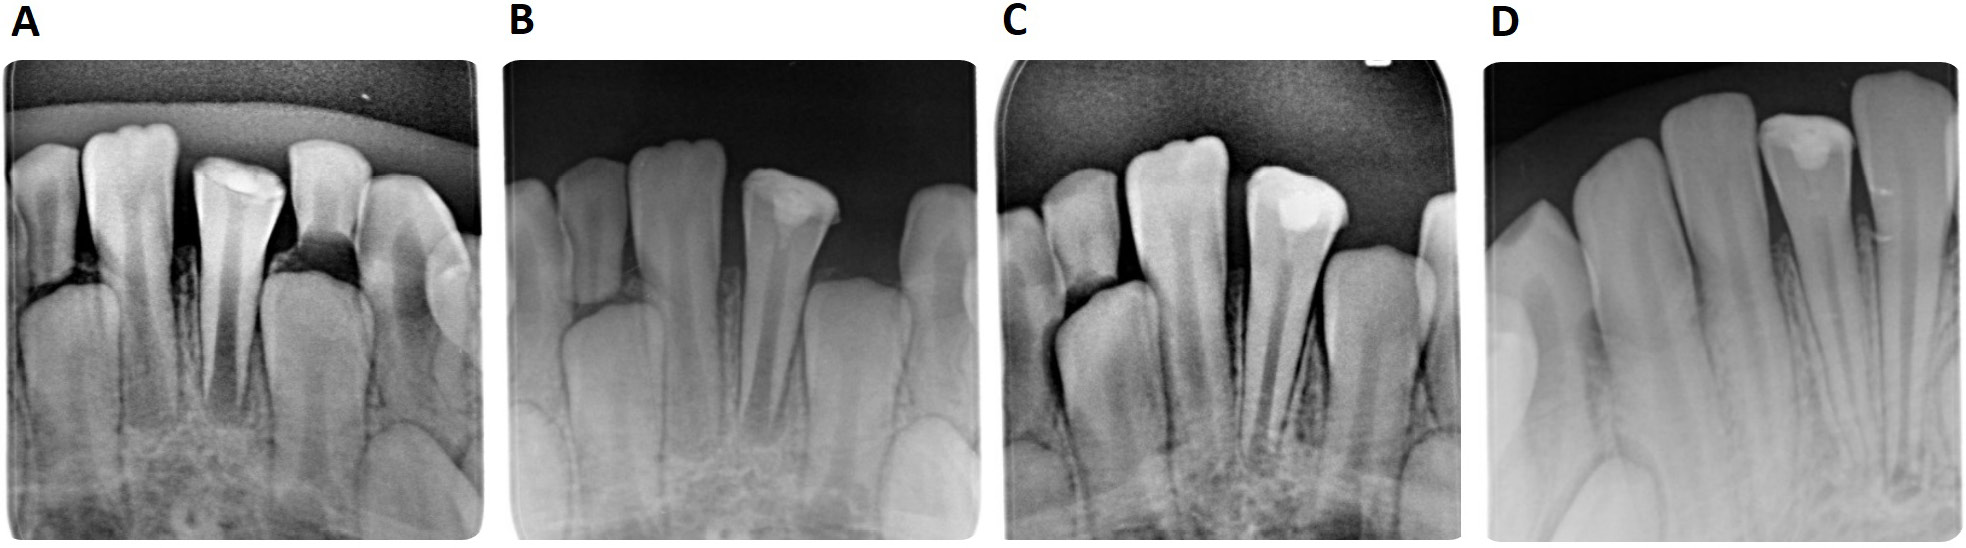

VPT success rate

The success rate analysis showed a success rate of 93.02% in the PBM group (40/43) and of 81.4% (35/43) in the control group. The overall success rate of VPT in our study was 87.2% (75/86). This showed a recorded failure of VPT in 11 cases in total. Three cases failed in the PBM group and 8 in the control group. No statistically significant difference was observed in success rates between the groups (p = 0.10646, Table 4). The radiological treatment success is presented in Figure 2.